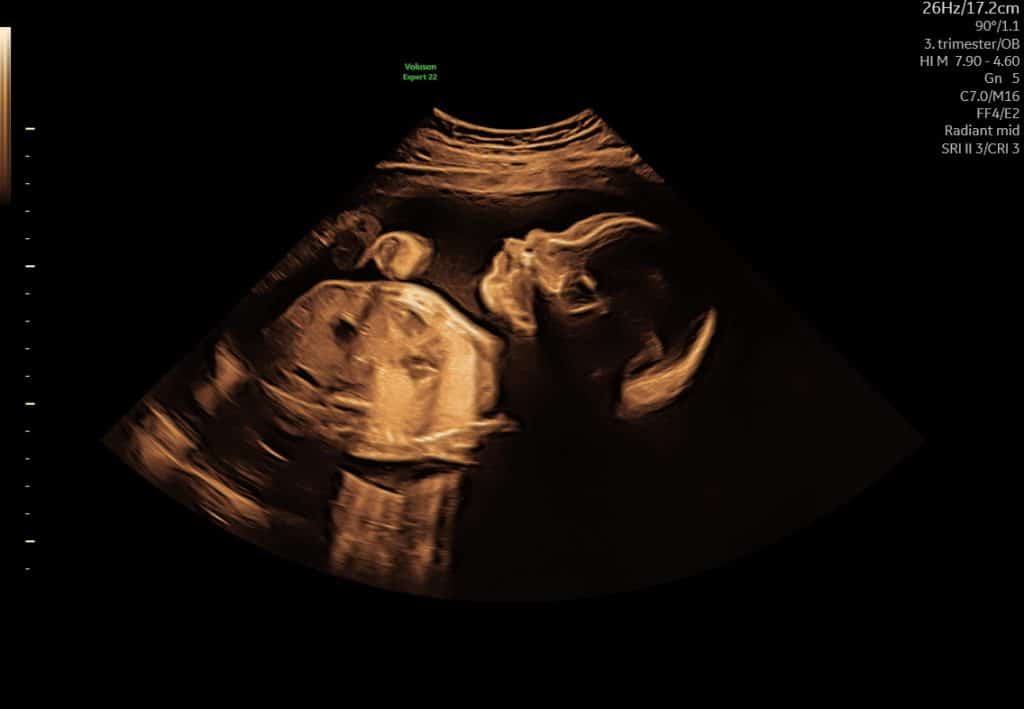

Tredje trimester (uge 28+)

Tilvækstscanning, 3D/4D-scanning og op/ned-scanning. Barnets leje og størrelse vurderes.